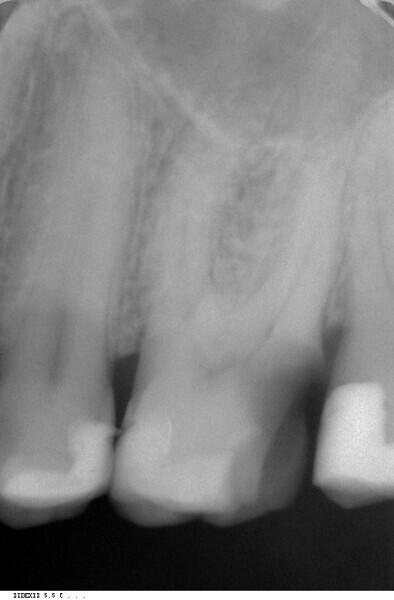

Endodontic follow-up in strongly curved root canals